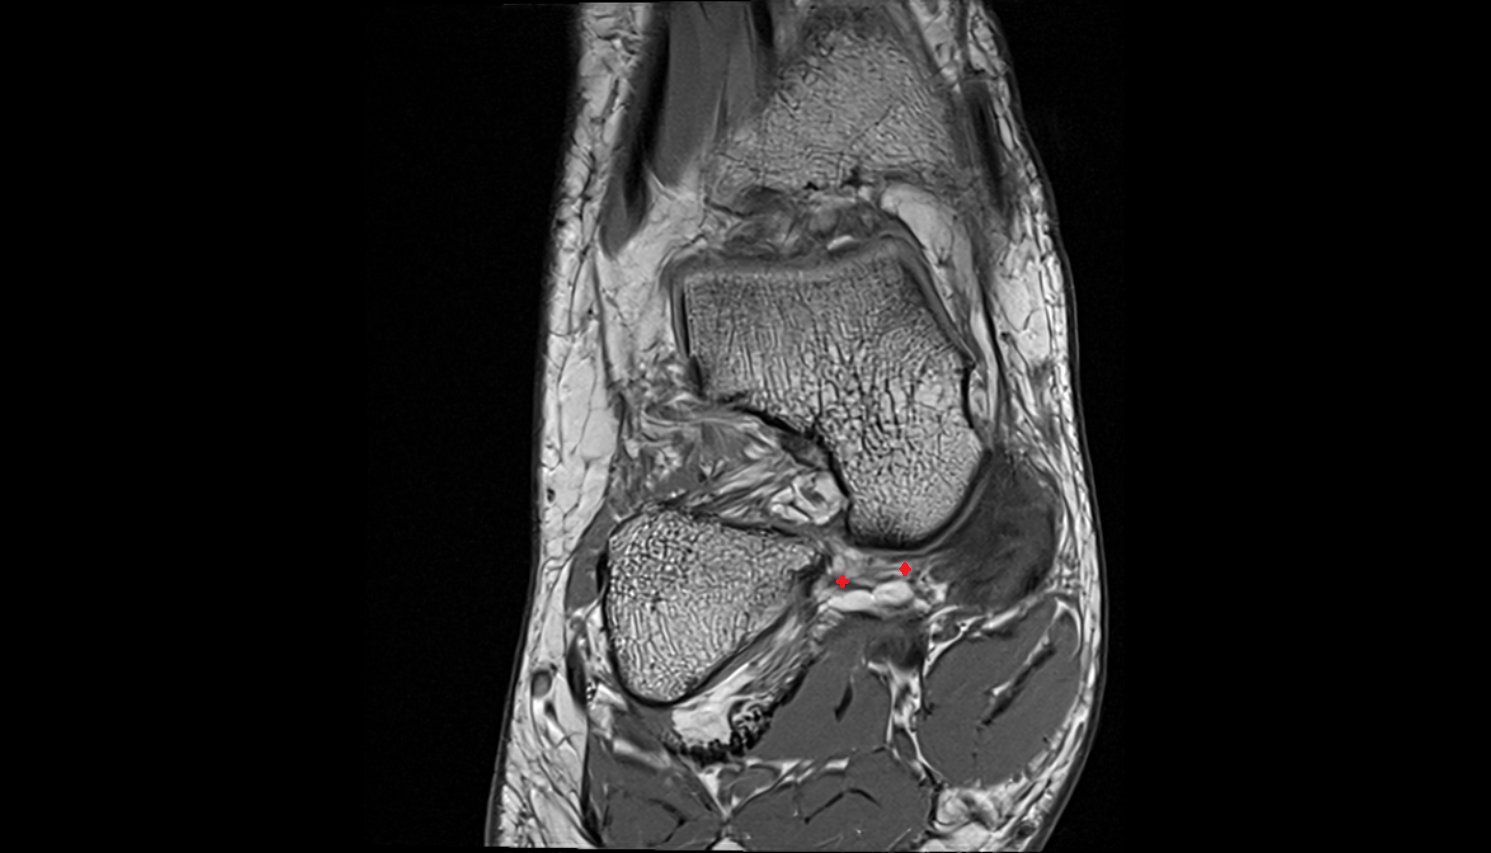

- Talus

- Body of talus

- Neck of talus

- Calcaneus

- Sustentaculum tali

- Talocalcaneal joint

- Talocalcaneonavicular joint